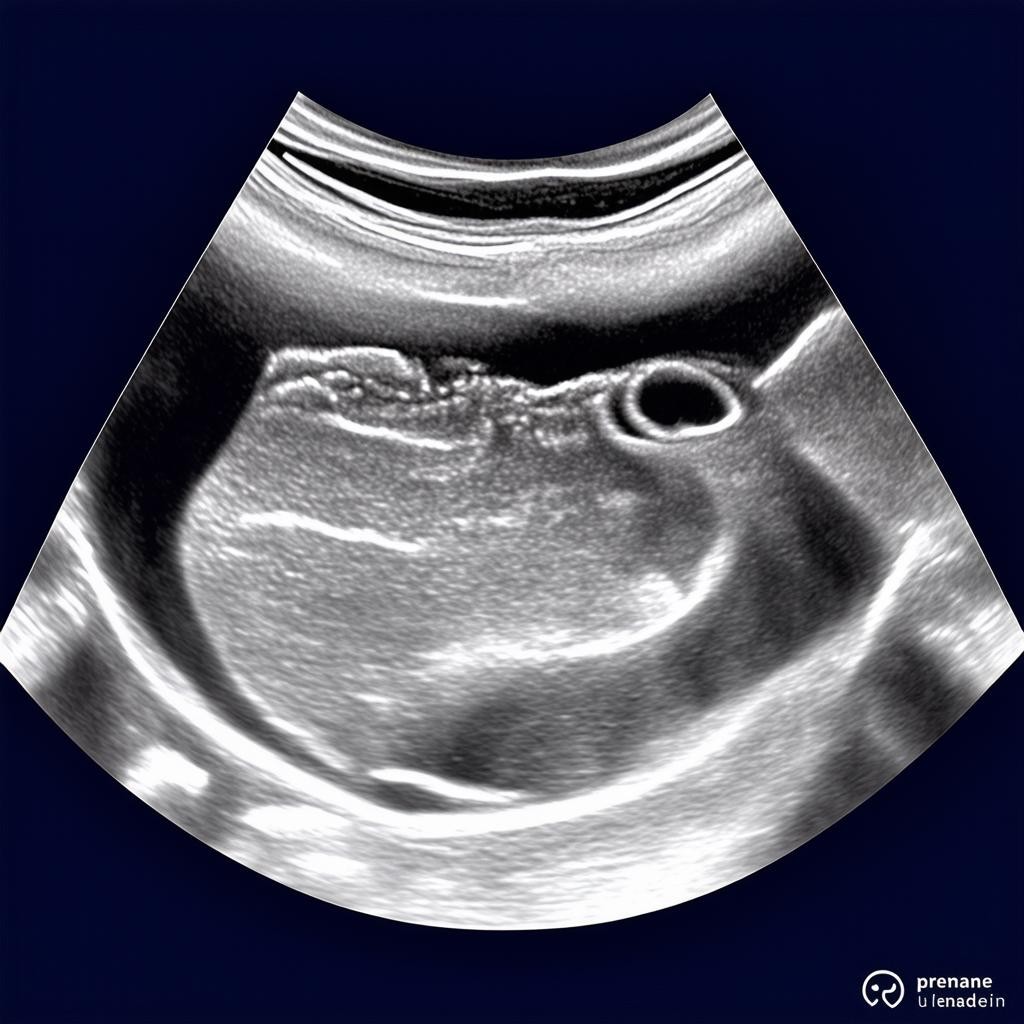

Вес ребенка на 33 неделе беременности: норма по УЗИ

33 неделя беременности — это важный этап в развитии плода. В этот период ребенок активно растет и набирает вес, готовясь к появлению на свет. По данным УЗИ, норма веса плода на 33 неделе составляет примерно 1900–2200 граммов, а его рост достигает 42–44 см. Однако эти показатели могут варьироваться в зависимости от индивидуальных особенностей.